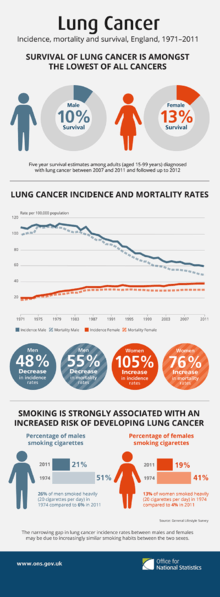

Of all people with lung cancer in the US, 16.8% survive for at least five years after diagnosis.[17][133] In England, between 2005 and 2009, overall five-year survival for lung cancer was less than 10%.[134] Outcomes are generally worse in the developing world.[18] Stage is often advanced at the time of diagnosis. At presentation, 30–40% of cases of NSCLC are stage IV, and 60% of SCLC are stage IV.[12] Survival for lung cancer falls as the stage at diagnosis becomes more advanced: the English data suggest that around 70% of patients survive at least a year when diagnosed at the earliest stage, but this falls to just 14% for those diagnosed with the most advanced disease.[135]

Worldwide in 2012, lung cancer occurred in 1.8 million people and resulted in 1.6 million deaths.[4] This makes it the most common cause of cancer-related death in men and second most common in women after breast cancer.[16] The most common age at diagnosis is 70 years. Overall, 17.4% of people in the United States diagnosed with lung cancer survive five years after the diagnosis,[17] while outcomes on average are worse in the developing world.[18]

The population segment most likely to develop lung cancer is people aged over 50 who have a history of smoking. In contrast to the mortality rate in men, which began declining more than 20 years ago, women's lung cancer mortality rates have been rising over the last decades, and are just recently beginning to stabilize.[143] In the USA, the lifetime risk of developing lung cancer is 8% in men and 6% in women.[6]